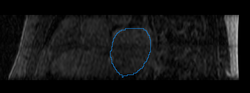

We then align the MRA and DE-MRI images of the same patient, which allows us to transfer the left atrium segmentation using the resulting deformation field. This is shown in the following figures.

Mdepa MRA MDE registration.png Mdepa MDE la segmentation.png